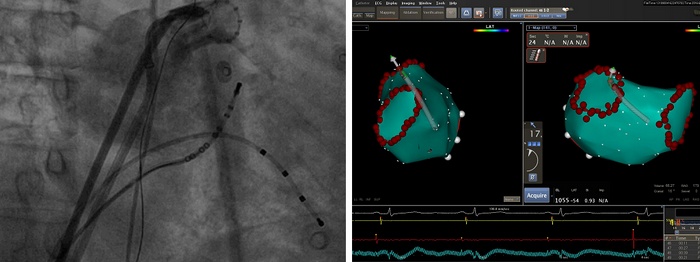

6月19日和21日,我院心内科先后顺利完成两例房颤射频消融术,哈特瑞姆医生集团提供技术支持,术后患者均恢复正常心律,无任何不适。短时间内两例手术的成功开展标志着我院心内科在心律失常介入治疗领域取得重大突破,房颤射频消融治疗已成为心内科的常规治疗手段。

患者杜先生,69岁,胡先生,53岁,均是近1年来反复发作心悸、自觉心跳不齐,伴有头晕、出汗。其中杜先生还患有冠心病,曾接受冠脉介入治疗,植入支架两枚,心悸严重时胸闷症状明显。心电图及24小时Holter检查诊断阵发性房颤,发作时心率最快可达150次/分,尝试多种抗心律失常药物治疗无效,症状发作愈发频繁、持续时间逐渐延长,患者难以耐受,严重影响日常生活,治疗意愿强烈,均希望根治房颤。我院心内科经充分讨论后认为两位患者均有房颤射频消融术指征。完善经食道心脏超声排除左心耳血栓后,分别于6月19日、6月21日进行房颤射频消融手术。在哈特瑞姆集团刘兴鹏教授的技术支持、导管室同事的全力配合下顺利完成手术,术后患者均恢复正常心律,无任何不适。

射频消融手术是根治房颤的介入治疗手术。该手术通过穿刺静脉血管,将2-3mm粗的电极导管送入左心房、肺静脉内进行三维建模,对房颤病灶进行精细标测,利用射频消融能量损毁心房、肺静脉口部的异常电活动组织,以达到根治房颤的目的。